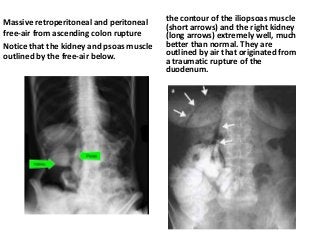

Plain abdominal radiographs

• are typically normal in patients with mild diverticulitis,

• but in the setting of severe disease, there may be an

ileus pattern, or, if obstruction is present, proximal

bowel dilation. A large abscess may be associated with

an air-fluid level on upright films. If there is perforation

into the retroperitoneal space, the psoas shadow may

be obliterated due to air diffusing along the psoas

muscle. Free air under the diaphragm may be seen on

upright films in the setting of intraperitoneal

perforation, especially if there is feculent peritonitis.

Massive retroperitoneal and peritoneal

free-air from ascending colon rupture

Notice that the kidney and psoas muscle

outlined by the free-air below.

the contour of the iliopsoas muscle

(short arrows) and the right kidney

(long arrows) extremely well, much

better than normal. They are

outlined by air that originated from

a traumatic rupture of the

duodenum.